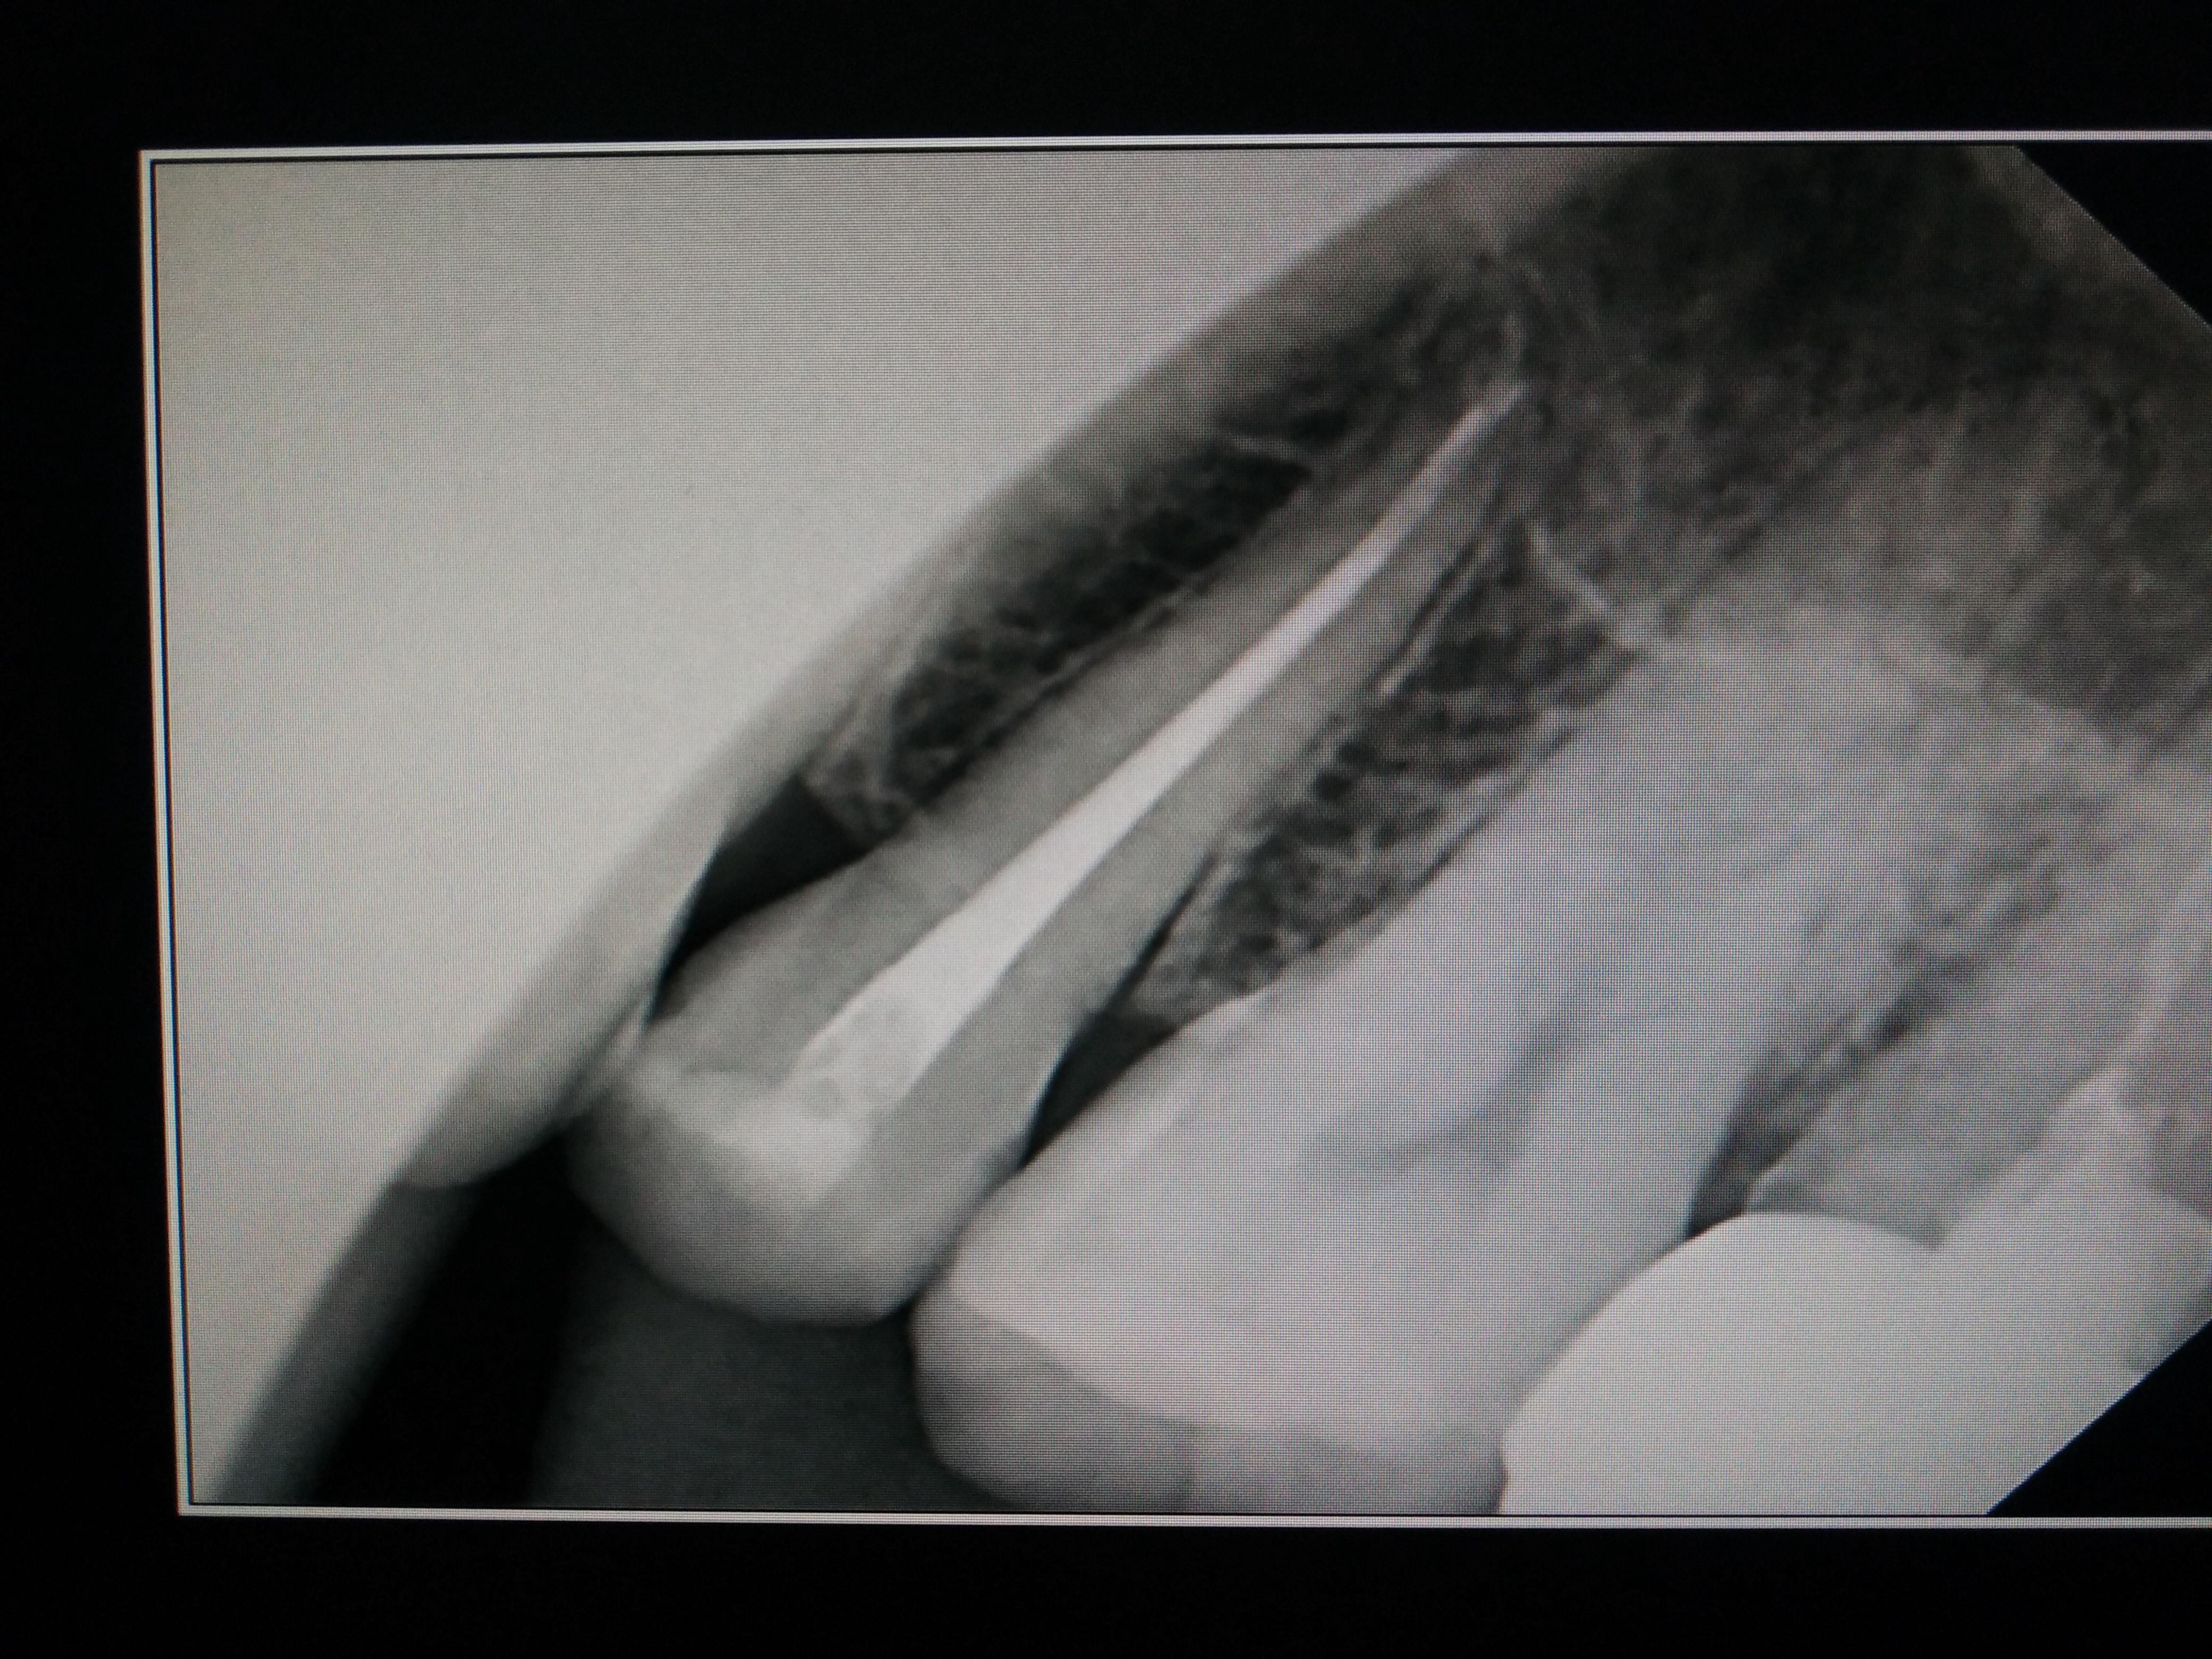

牙片看根管侧穿底穿和根裂

根管治疗三个月了还是自发痛,现疼痛减轻不少,偶尔一跳一跳的痛,偶尔酸;摇患牙酸酸的感觉,请大家看看该牙有异常吗,暂封的药物,还未根充。小牙片从左数第一颗,是上牙五号。谢谢!

根折了,很明显啊,看不出来吗?